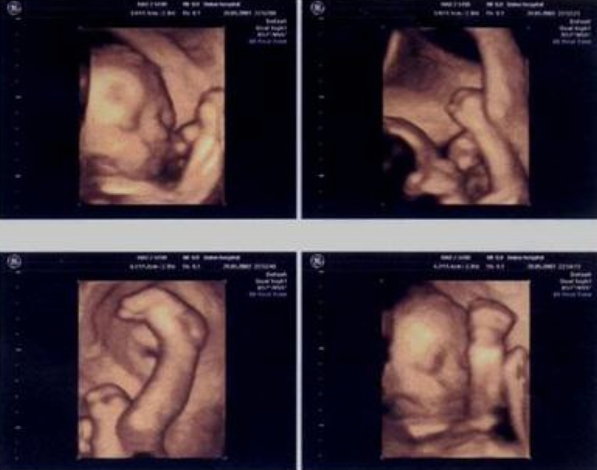

何英在接受采访时提到,“我和较胖的孕妇沟通的时候,经常会和她们打一个比方,假如医生是司机,肚皮薄、腹壁声窗条件好的孕妇,就是一个晴天的视线,得到的超声图像质量好,”何英说道,“而肚皮厚、腹壁声窗条件差的孕妇,好比是一个浓雾天,得到的图像质量差,更甚至有的连颅内的结构,如脉络丛、侧脑室、小脑都看不清,心脏只能看到在跳动,四腔心结构、房室瓣的启闭等都看不见。”

“这种情况我们做医生的实在是无能为力,再加上很多人对B超不了解,总是会去误解医生。”何英说,“很多人对技术的问题不了解,认为不受其他条件影响,其实不然,B超受一些潜在因素的影响,比如腹壁脂肪厚会导致声衰减,图像质量差;胎儿某些体位也会影响一些部位的观察;羊水过多时胎儿活动频繁,难以获取标准切面;羊水过少时缺乏良好的羊水衬托,胎儿结构难度显示加大等。”